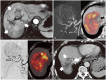

Yttrium-90 transarterial radioembolization (TARE) has emerged as a valuable treatment option for hepatocellular carcinoma (HCC) and is being increasingly incorporated into clinical guidelines. Recent advancements in dosimetry, including personalized dosimetry and multi-compartment modeling, have significantly improved tumor response and clinical outcomes. Although high tumor-absorbed doses are associated with better oncologic control, careful dose adjustment is essential for minimizing toxicity to normal liver tissue and lungs. This review explores the key aspects of TARE dosimetry, including single- and multi-compartment modeling, differences between resin and glass microspheres, dose-response relationships, and strategies to mitigate hepatotoxicity and radiation pneumonitis. Various clinical applications of TARE have been discussed, ranging from curative-intent radiation segmentectomy and lobectomy to palliative treatment of diffuse and macrovascular invasion-associated HCCs. In South Korea, where cadaveric liver transplantation is limited, a multidisciplinary approach is particularly important for optimizing treatment strategies and preserving liver function for potential future interventions. As dosimetry continues to evolve, further research is required to refine dose optimization protocols and validate their clinical impact in different patient populations, including those in South Korea.